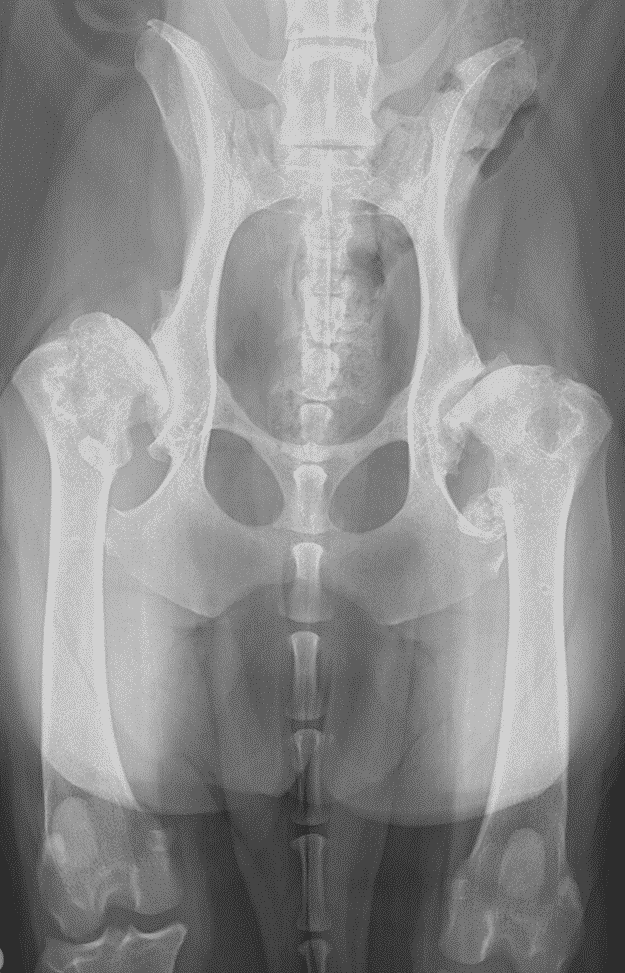

Even though there is limited association between radiographic and clinical signs of dysplasia, when both are severe, dogs are likely to benefit from early total hip replacement (Figures 1 and 2). In young dogs, the typical example is an eight- to nine-month-old medium to large-breed dog with luxoid hips which cannot walk for more than 10 to 20 minutes (Figure 2). These patients often only partially respond to conservative management and waiting for too long before a total hip replacement surgery may compromise its outcome. These dogs may experience remodelling of their proximal femoral metaphysis and diaphysis which may preclude the use of conventional implants or the chronically luxated hip may be extremely challenging to reduce in the future.